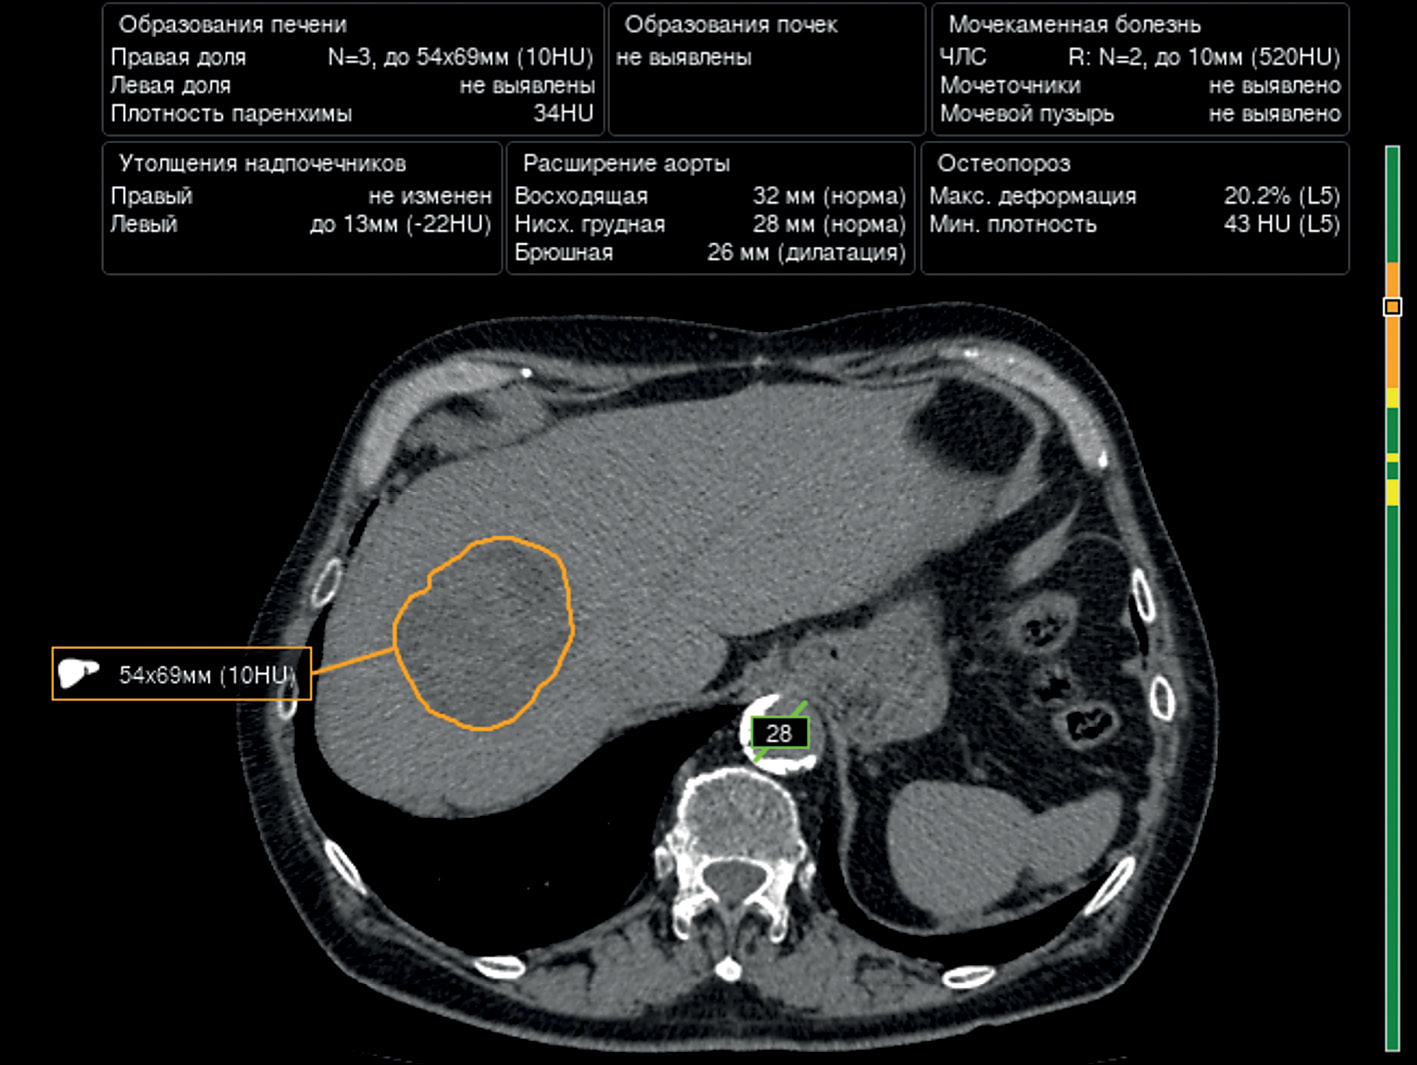

The U-Net architecture and its modifications (i.e., ResNet blocks) are most widely used for segmentation of the liver and liver neoplasms, with acceptable diagnostic accuracy. H. Rahman et al. demonstrated the best results for the segmentation of the liver and liver neoplasms using ResUNet, with a Dice coefficient of 0.09 and an accuracy of 99.6% [12]. An example of liver neoplasm segmentation is presented in Fig. 1.

Fig. 1. An example of liver neoplasm segmentation using one of the algorithms.

The Center for Diagnostics and Telemedicine (Moscow) is currently developing a computer vision algorithm using contrast enhancement for within-class segmentation and differentiation of liver masses. An example is presented in Fig. 2.

Fig. 2. An example of liver neoplasm segmentation by an algorithm based on a contrast-enhanced CT scan.